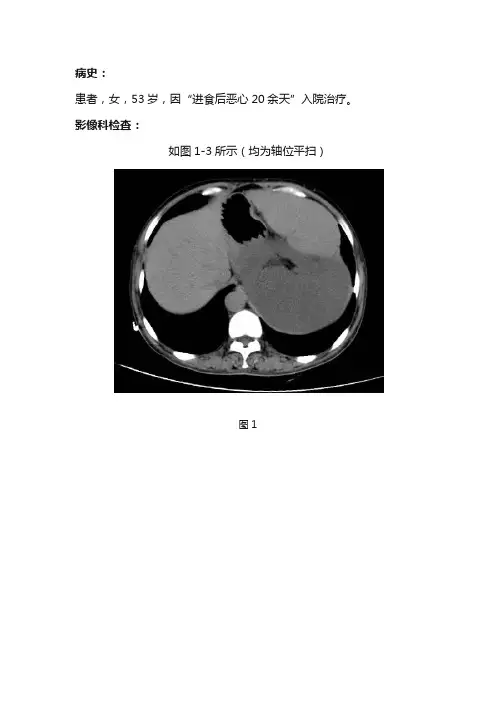

病史:患者,女,53岁,因“进食后恶心20余天”入院治疗。

影像科检查:如图1-3所示(均为轴位平扫)图1图2图3基础解剖影像:图4 CT门脉期胰腺水平图5 CT门脉期胰腺水平腹膜后彩色示意图图6 CT门脉期肾脏水平图7 CT门脉期肾脏水平腹膜后彩色示意图图8 CT门脉期肾门水平图9 CT门脉期肾门水平腹膜后彩色示意图图10 CT门脉期结肠水平图11 CT门脉期结肠水平腹膜后彩色示意图图4-11所示分别为正常成人腹部增强门脉期胰腺水平、肾脏水平、结肠水平轴位图像及腹膜后彩色示意图(节选自《CT与MRI断层解剖学袖珍图谱-心胸腹盆》),CT图像中因口服对比剂,胃肠道内可见高密度对比剂影,彩色示意图中黄色区域为腹膜后区域,包括胰腺、双肾等组织器官。

图1图2图3图1-3所示腹部平扫:左腹及腹膜后见团块样不均匀软组织密度影(蓝色箭头),上至左侧横膈、下至髂总动脉分叉处水平、大小约为19.8cmX13.2x29.3cm,其内见条样钙化影及多发片状脂肪样低密度(黄色箭头),腹腔内相邻脏器受压右移。

影像诊断:左腹及腹膜后巨大占位病变,考虑脂肪肉瘤。